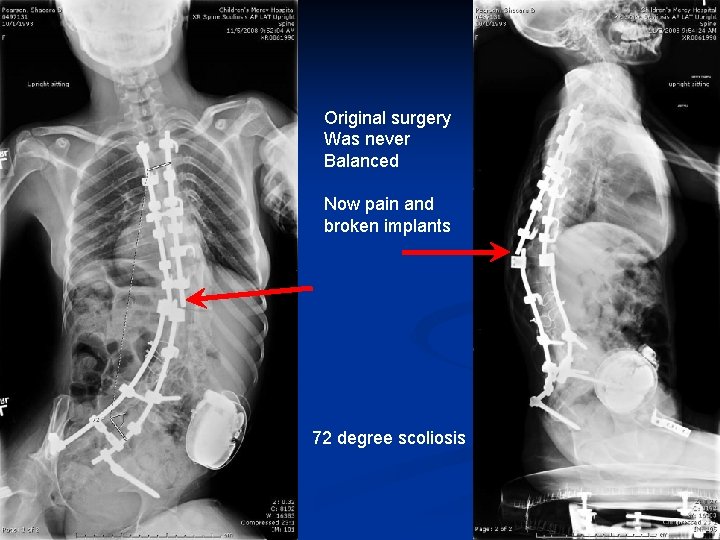

n n Case 3: Intraoperative compression for SPO in fixed deformity 15 year old female CP GMFCS 4 progressive neuromuscular scoliosis. Motor WC PSFI at age 10 years. Never was happy with post op balance. Difficulty sitting. Iliac screw eroding through skin and severe back pain.

Original surgery Was never Balanced Now pain and broken implants 72 degree scoliosis